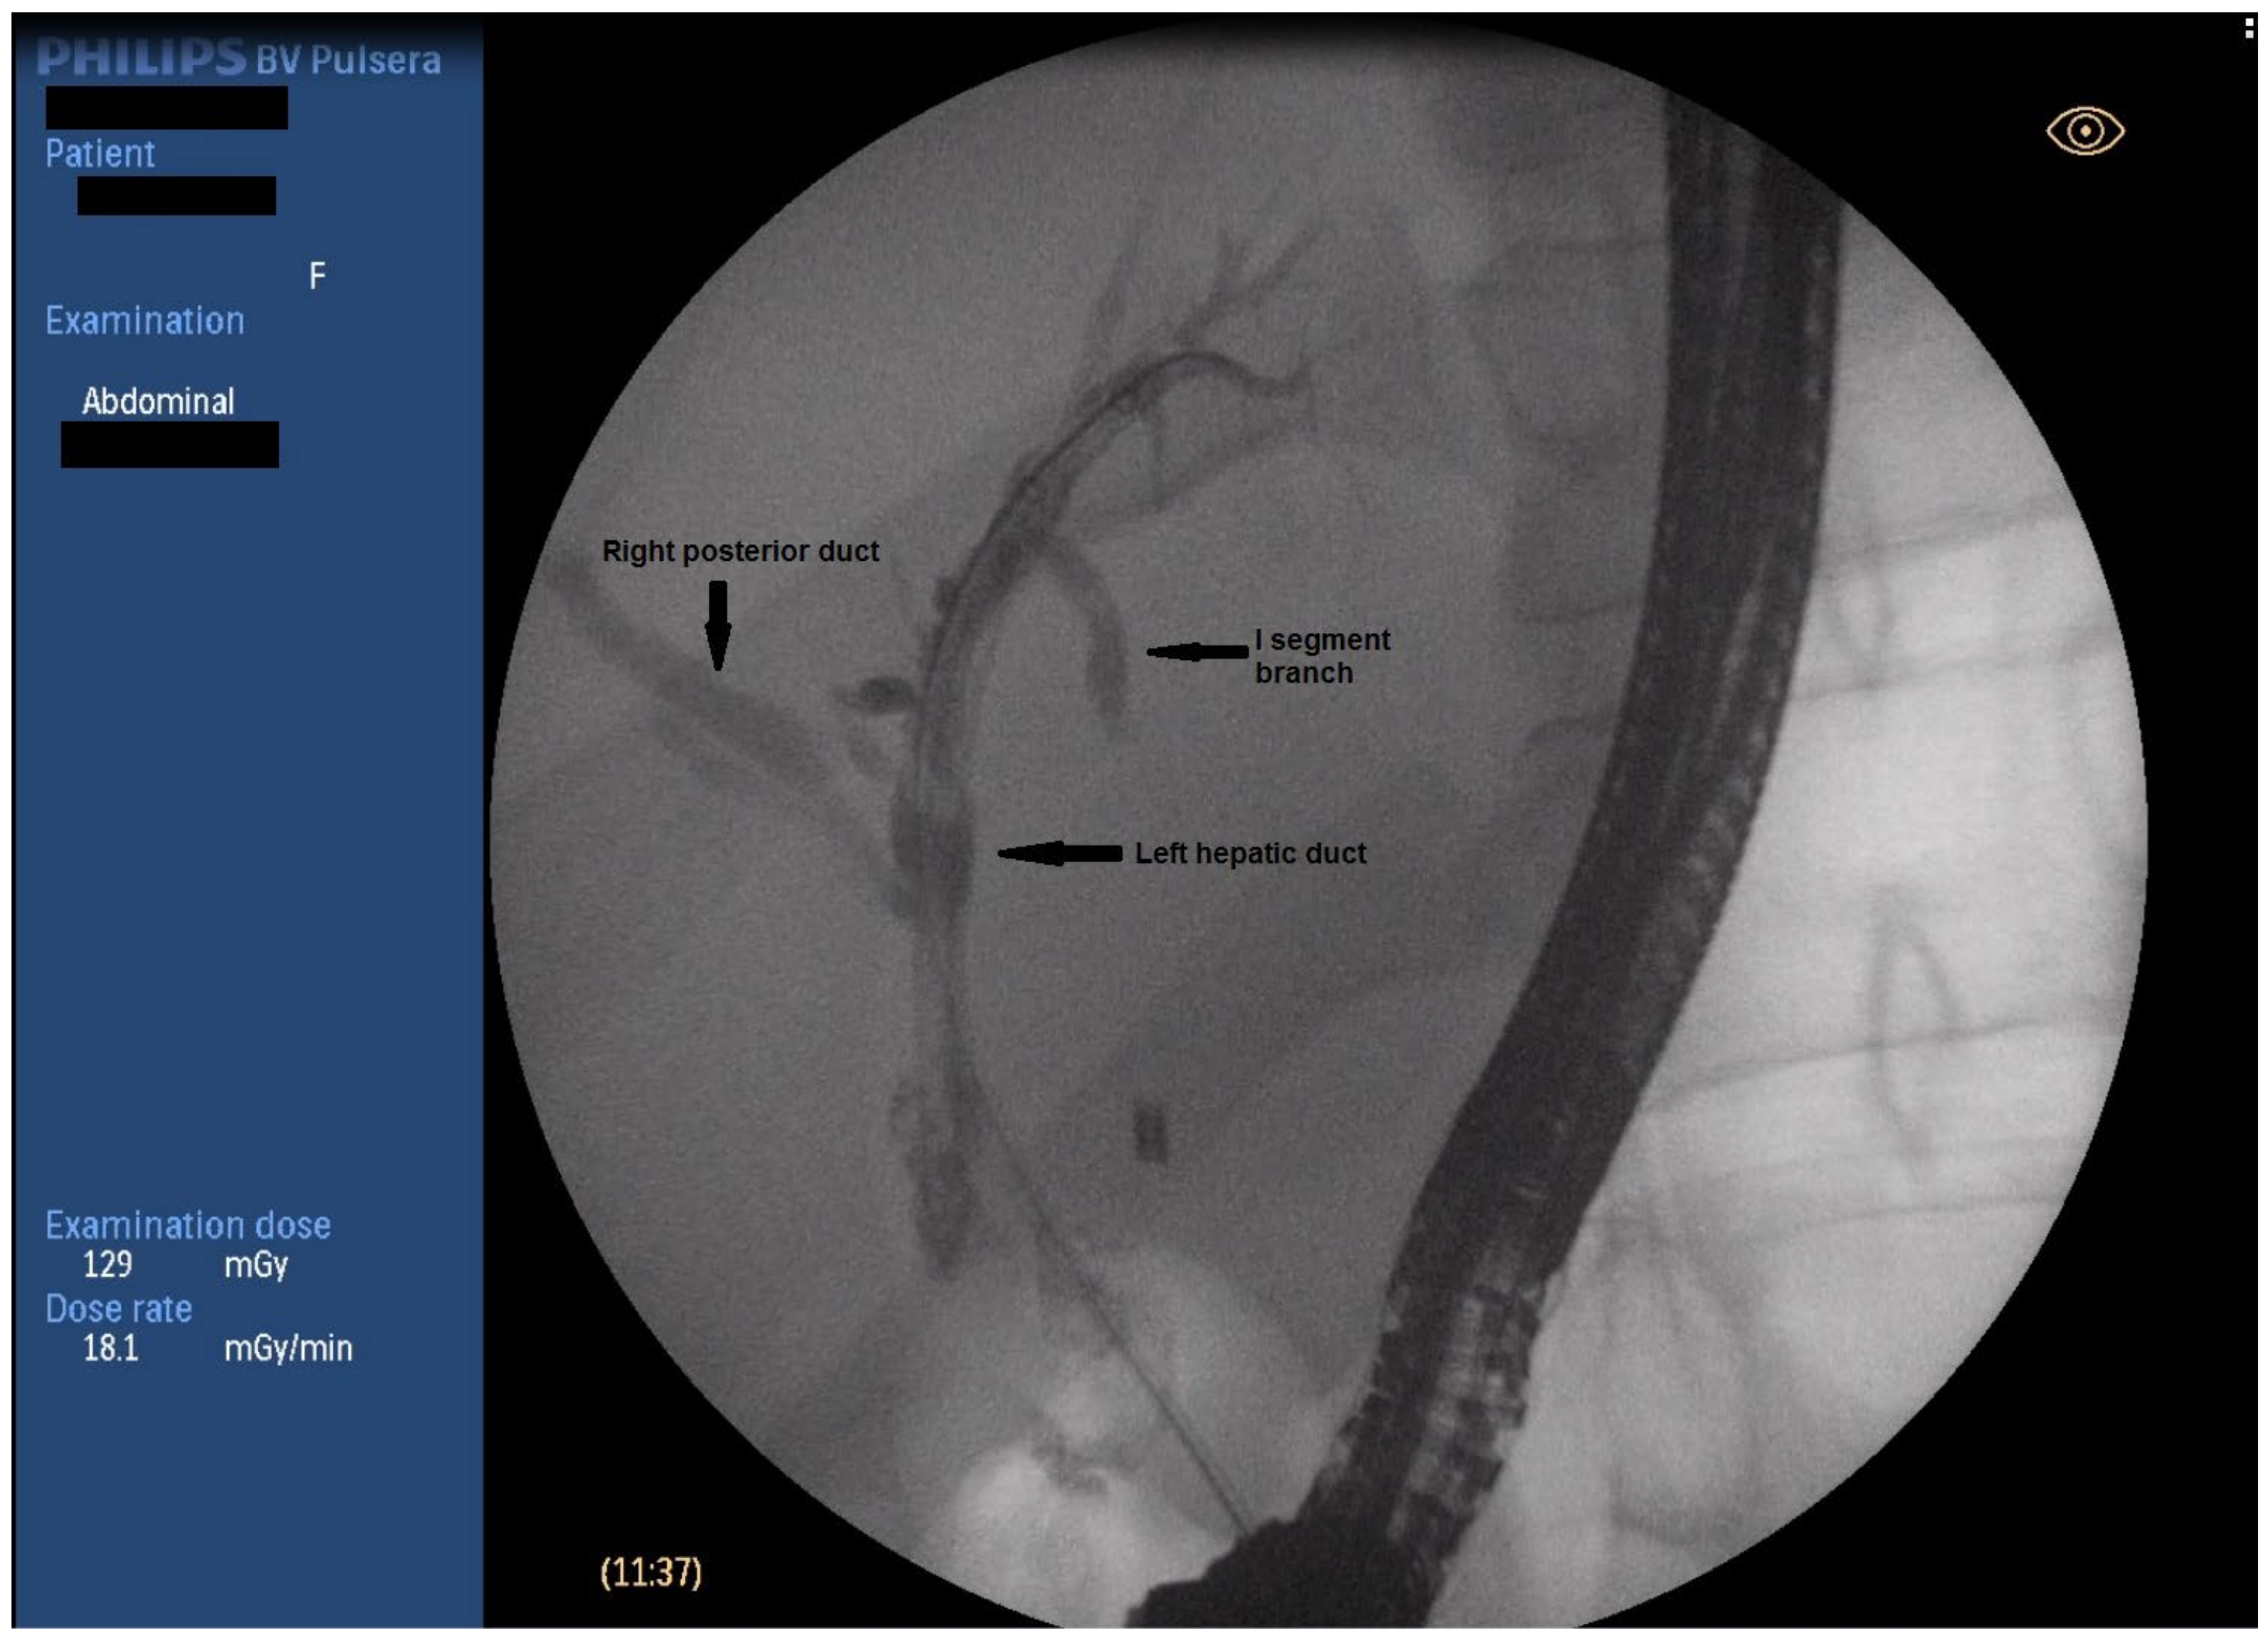

2.3. Endoscopic Management

Figure 2. Fluoroscopic image of biliary anatomy.